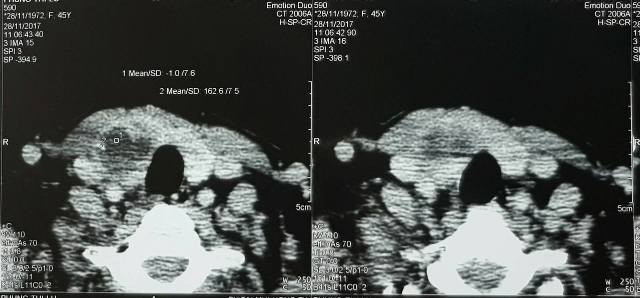

Kết quả cho thấy có một ổ áp xe, hình ảnh trên phim cắt lớp thấy thuỳ P tuyến giáp có 1 khối giảm tỉ trọng và bên trong có hình ảnh cản quang nghi ngờ dị vật, tuy nhiên ban đầu chưa khẳng định đó có phải chắc chắn là xương hay không.

Qua thăm khám của các bác sĩ phòng cấp cứu đánh giá khả năng nghi ngờ một ổ áp xe tuyến giáp, hình ảnh dị vật cản quang qua rất nhiều lớp trong ở giảm tỷ trọng có thể nghĩ đến hình ảnh một chiếc xương cá (do bệnh nhân có tiền sử hóc xương sau khi ăn cá).